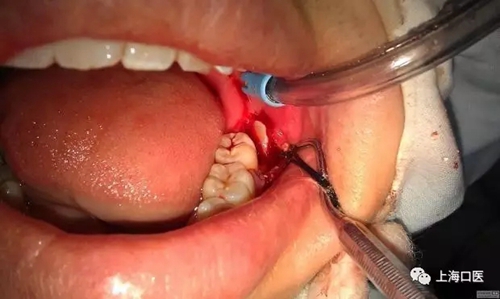

智齒拔除

拔牙干槽癥可怕嗎?

縫合